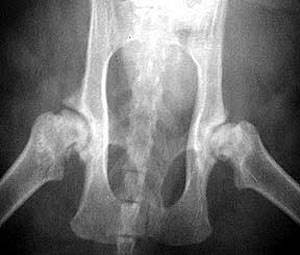

При дисплазии тазобедренных суставов (ДТБС) поверхности тазобедренного сустава не соответствуют друг другу. Этому заболеванию подвержены все собаки крупных пород, особенно немецкая овчарка, золотистый ретривер, лабрадор-ретривер, боксер.

ДТБС не лечится до конца, но можно снизить влияние дефекта на самочувствие животного, при этом следует строго контролировать вес животного и нагрузку на тазобедренные суставы, например, ограничить прыжки и подъем по лестнице. Следует укреплять окружающую суставы мускулатуру посредством легкой физической нагрузки: бег небыстрой рысью, плавание и ходьба в воде (этим целям отлично отвечает водная беговая дорожка). В сложных случаях показана хирургическая операция, имеется множество методов коррекции, которые необходимо обсудить с ветеринарным врачом - специалистом (ортопедом).